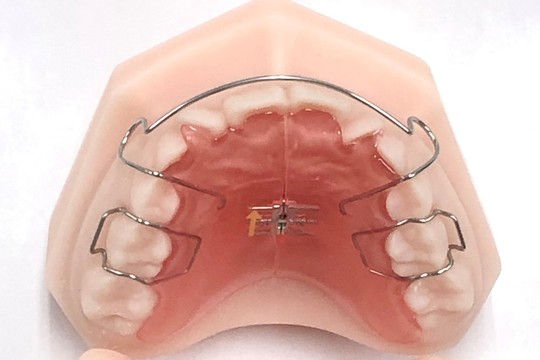

床矯正

矯正といったらお馴染み“ブラケット装置”(ダイレクトボンドシステム(DBS))から、入れ歯型の床矯正装置(拡大床)、その他、内側で見えない3Dリンガルアーチ、歯列拡大の3Dクアドヘリックス、機能的マウスピース型矯正装置(マイオブレイス、プレオルソ、EFライン)、口腔筋機能療法(Myo Functional Therapy)、反対咬合にムー・シールドやパナシールド、下の前歯用のスプリングリテイナー、部分矯正、成人矯正など、口腔内の状況に合わせた様々な装置および治療法を選択いたします。

取り外し式の床矯正装置 ¥77,000